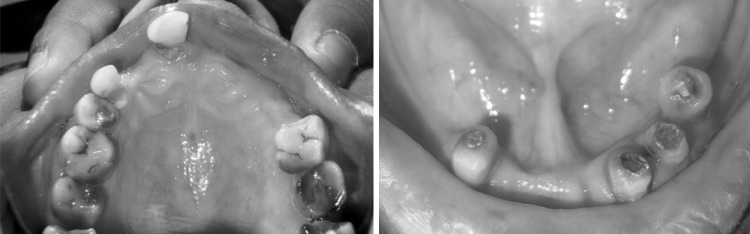

A 74-year-old man was referred to the department of prosthodontics at M.S. Ramaiah dental college, Bangalore. The medical history was non-contributory. Intraoral evaluation revealed partially edentulous maxillary and mandibular arch. Remaining teeth in mandibular arch were grade I mobile (Fig. 1). The patient was made aware of the situation and had expressed a desire to maintain the remaining teeth as long as possible. In mandibular arch remaining teeth were root canal treated, minimal vestibular depth and severe resorption in relation to bilateral mandibular posterior ridge. Others oral findings were unremarkable.

Fig. 1.

Pre-operative upper and lower arch (mandibular teeth were endodontically treated)